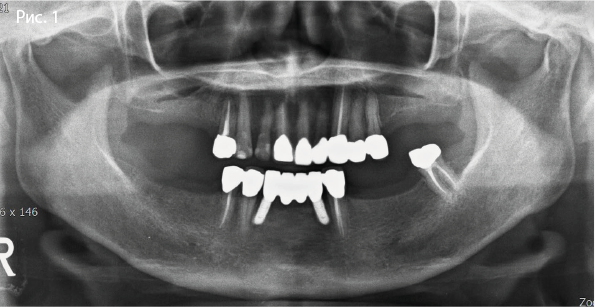

• Панорамная рентгенограмма: выраженная атрофия дистальных отделов нижней челюсти

Исходная панорамная рентгенограмма